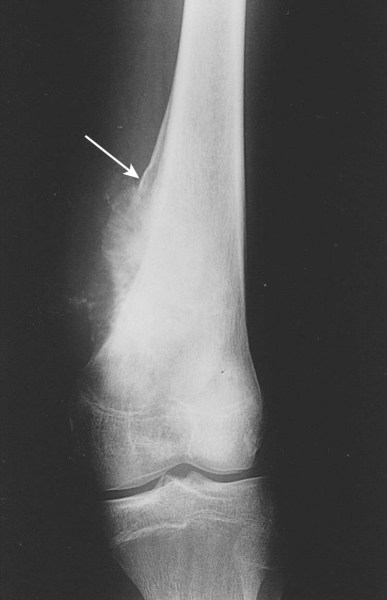

Osteosarcomas arise in the metaphyseal region of the long bones and may extend into the diaphyseal or epiphyseal region or both of the affected bone. Cortical bone is destroyed and a periosteal reaction gives rise to the Codman's Triangle and periosteal spicules. A soft tissue mass is usually present and can be seen on MRI. MRI can also image intermedulary skip metastases.